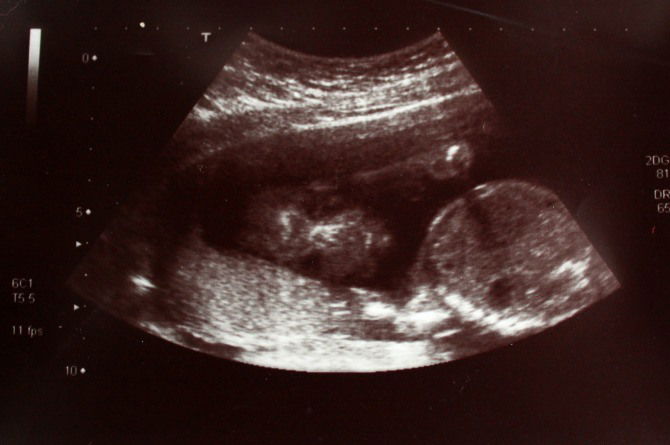

Hormones not firing at the right time

Image source: iStock

According to doctors, here’s why we have Guevedoces:

Upon conception, baby boys get the X and Y chromosomes which tell their bodies to produce specific hormones. These hormones tell their cells to grow a penis and testes in the womb.

With the case of the Guevedoces, the hormones that tell the body to create a penis and testes aren’t released until they hit puberty. So until the hormones are released at twelve, they have what looks like female private parts.